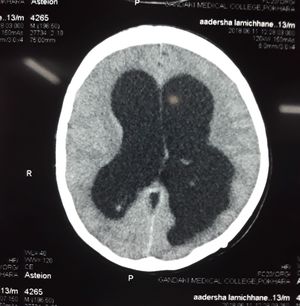

Non-communicating Hydrocephalus at right lateral ventrical

There is an obstruction making there a long narrow pathway between the 3rd and 4th ventricles. Due to a mass of something? There is clear build up of spinal fluid.